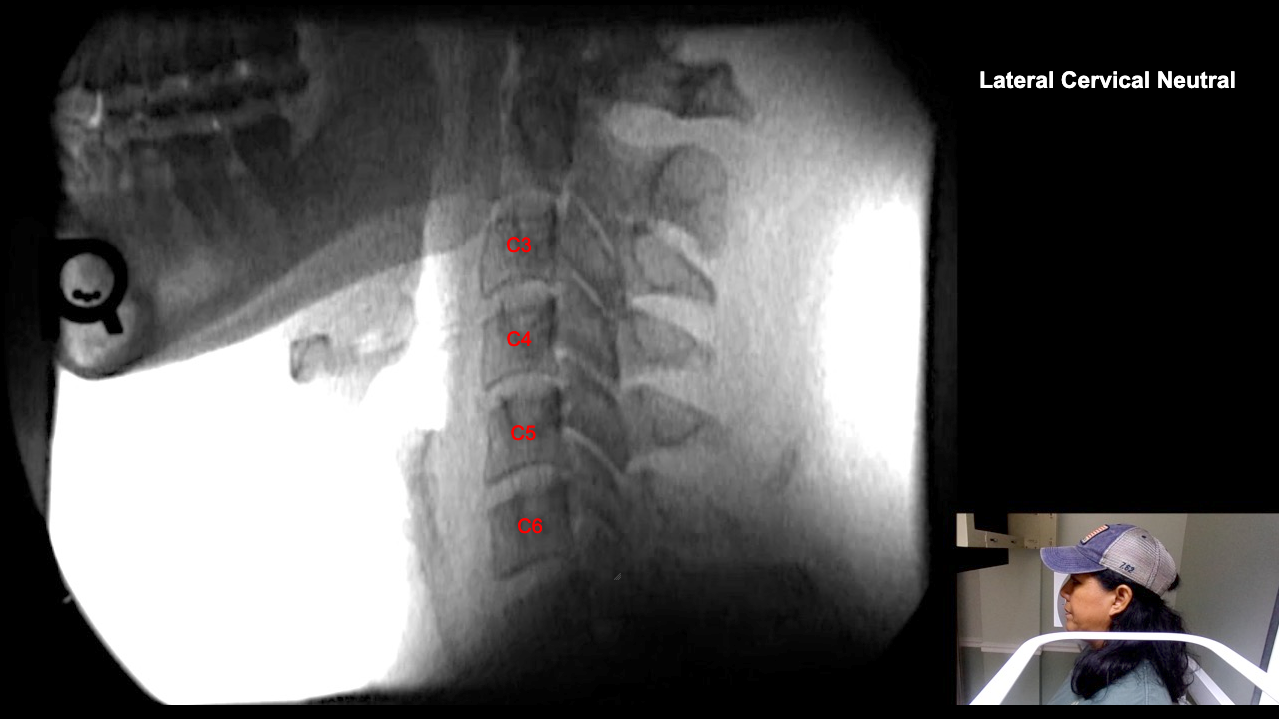

Image Name Image Type Image

Image 2